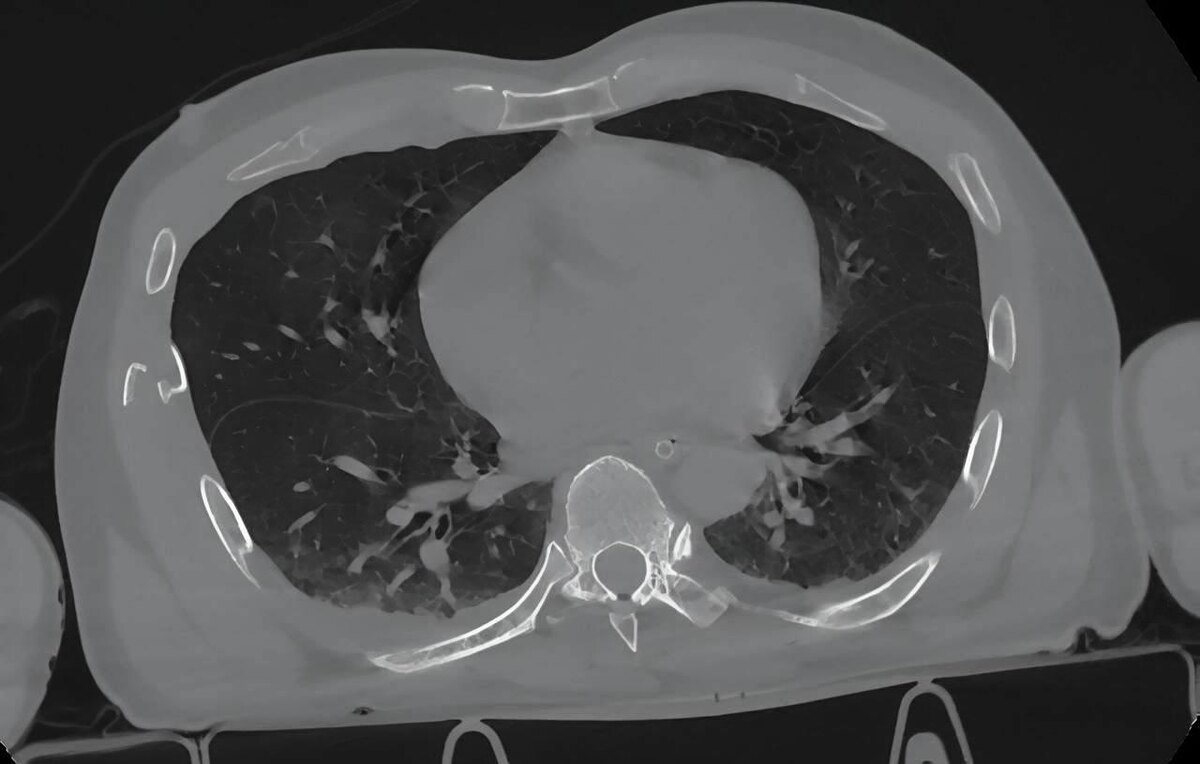

Врачи диагностировали сочетанную травму: разрывы печени, брыжейки, тонкой кишки и мочевого пузыря, повреждение селезёнки (её пришлось удалить), множественные переломы рёбер с двух сторон с кровоизлиянием в грудную полость, ушиб сердца, нестабильный перелом таза и закрытые переломы голени со смещением.